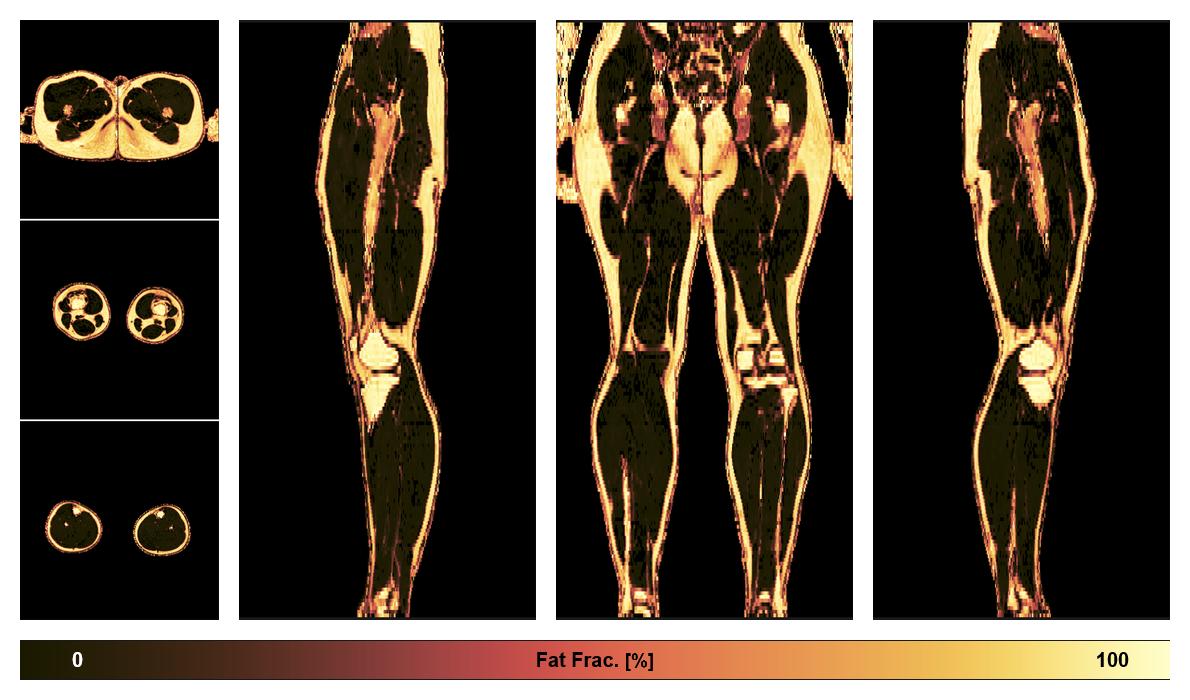

Water-fat quantification

Dixon based water fat quantification, for information look here».

• Fat fraction

The fat fraction of the lower extremity obtained from the dixon reconstruction for muscle water fat quantification.